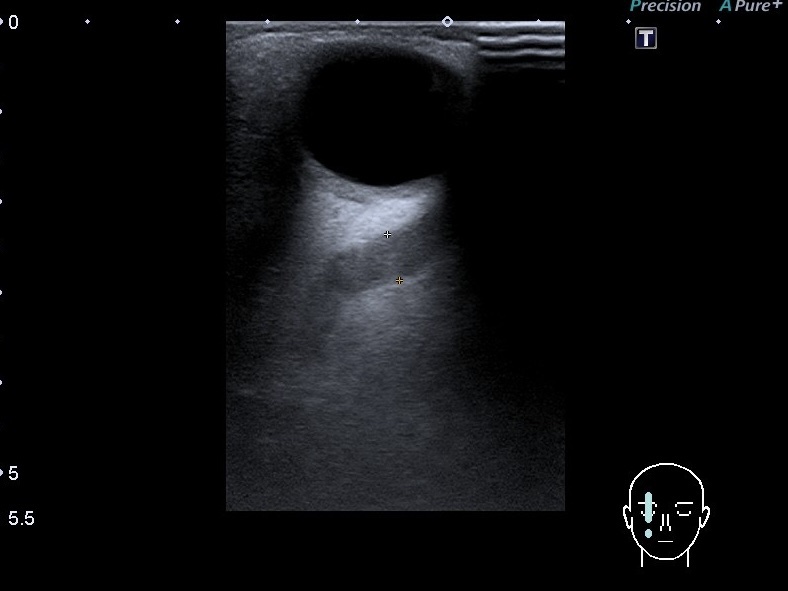

По спектру кровотока ми визначаємо, чи то венозний, чи то артеріальний кровотік. Але не завжди вена буде мати венозний спектр кровотоку. Наприклад ,буває так, що артерія і вена мають співустя(аномалія така). Каротидно-кавернозне, наприклад. Це коли внутрішня сонна артерія сполучається з кавернозним синусом. При цьому на УЗД ми бачимо анехогенну трубчасту структуру за оком. При включенні режиму кольорового доплеру виявлена структура буде розширеною верхньою очною веною. При визначенні спектра кровотока буде виявлений не венозний, артеріальний спектр кровотоку. На сканах представлений випадок такої вени, але ще й з тромбом, який частково розчинився(часткова реканалізація).